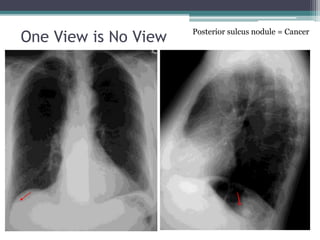

• One view is no view – use it all!

One View is No View Posterior sulcus nodule = Cancer

Basic Concepts • Oneview is no view – use it all! • Patterns are your clue • Be sure you are looking • Know what you’re looking for • Know the limits of your test

One View isNo View Posterior sulcus nodule = Cancer